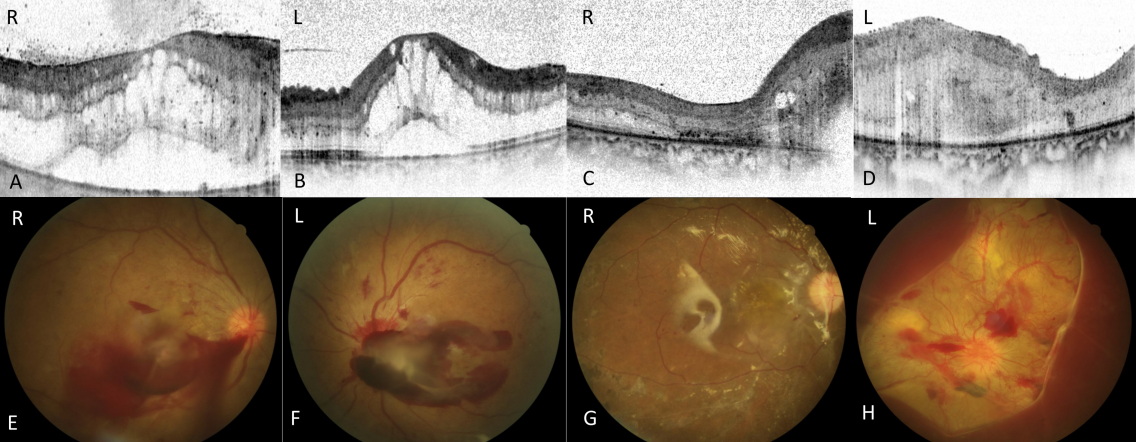

Two weeks after the C-section, both eyes still showed massive proliferations on the posterior pole, macular edema, tractive retinal membranes and bleeding (Figure 3 [Fig. 3]).

Figure 3: DR in preeclampsia.

A, B: OCT of patient 3 with DM type I at baseline showing bilateral cystic macular oedema (CME).

C, D: OCT at follow up (t= 6 month) showing a regressive CME in the right eye and fibrovascular material in the left eye.

E, F: Funduscopic image of patient 3 with DM type I at baseline showing bilateral preretinal hemorrhages.

G: Funduscopic image at follow up (t=6 month) showing a regression of preretinal hemorrhage.

H: Funduscopic image at follow up (t=6 month) showing an aggravation of the preretinal hemorrhage.

Both eyes underwent pars plana vitrectomy in a short period, with removal of tractive membranes, peeling of the inner limiting membrane, additional panretinal laser treatment and injection of intravitreal steroids (for the right eye) and anti-VEGF substances (both eyes).

A stable retinal condition was achieved 1.5 years after the initial complaint with a visual acuity of 20/400 in both eyes.